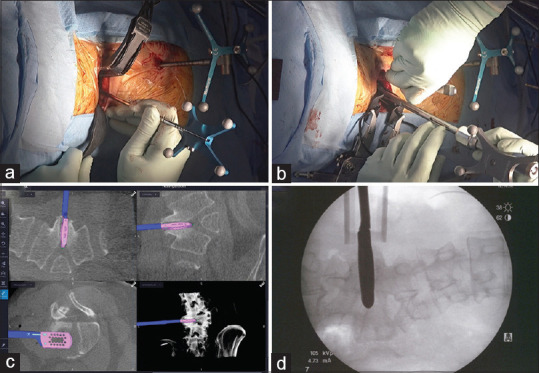

Hemivertebra is a rare congenital spinal anomaly often diagnosed in childhood due to progressive scoliosis. Initial diagnosis of hemivertebra in adulthood is uncommon, and standardized treatment protocols are not well established. This report presents a case of successful management of an L4 hemivertebra in an adult using oblique lateral interbody fusion (OLIF) with O-arm navigation. The patient, a 55-year-old, presented with chronic lower back pain and thigh pain exacerbated by standing and walking. Imaging studies revealed an L4 hemivertebra with mild scoliosis and foraminal stenosis caused by degenerative change. The patient underwent OLIF with O-arm navigation, followed by short-segment fixation with pedicle screws. Postoperative imaging confirmed appropriate implant positioning. The patient experienced complete resolution of symptoms except for mild sensory disturbance in the left thigh, with stable outcomes at the 2-year follow-up. The OLIF technique, guided by O-arm navigation, allowed precise adjustments to the anatomical characteristics of the hemivertebra, minimizing surgical invasion, and avoiding extensive corrective fixation. This approach resulted in favorable outcomes, suggesting its viability as a treatment for adult hemivertebra with minimal scoliosis. Furthermore, the use of intraoperative navigation addressed the anatomical abnormalities associated with adult hemivertebra, reducing the reliance on repeated fluoroscopic imaging and minimizing the risk of complications. OLIF with O-arm navigation is an effective and minimally invasive treatment option for adult hemivertebra, providing symptom relief and favorable outcomes.